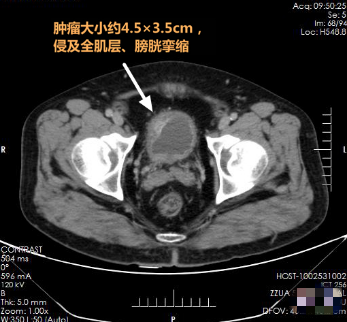

患者资料:男,63岁,发现间断肉眼血尿3余。入院超声、SCT检查提示:膀胱右前壁实性占位,侵及肌层,考虑膀胱癌。既往合并冠心病10年,先后3次行冠脉支架植入术,患高血压病、糖尿病8年余。术前评估手术麻醉风险较高。

术前

▲ 术前影像检查资料

术前诊断性电切:镜下见膀胱右侧前顶壁,局部粘膜粗糙,隆起于膀胱腔内,面积约5.5cm×3.5cm,切去肿瘤及基底部肌层分别送检,病理报告:肿瘤及基底部均为尿路上皮癌Ⅱ级。